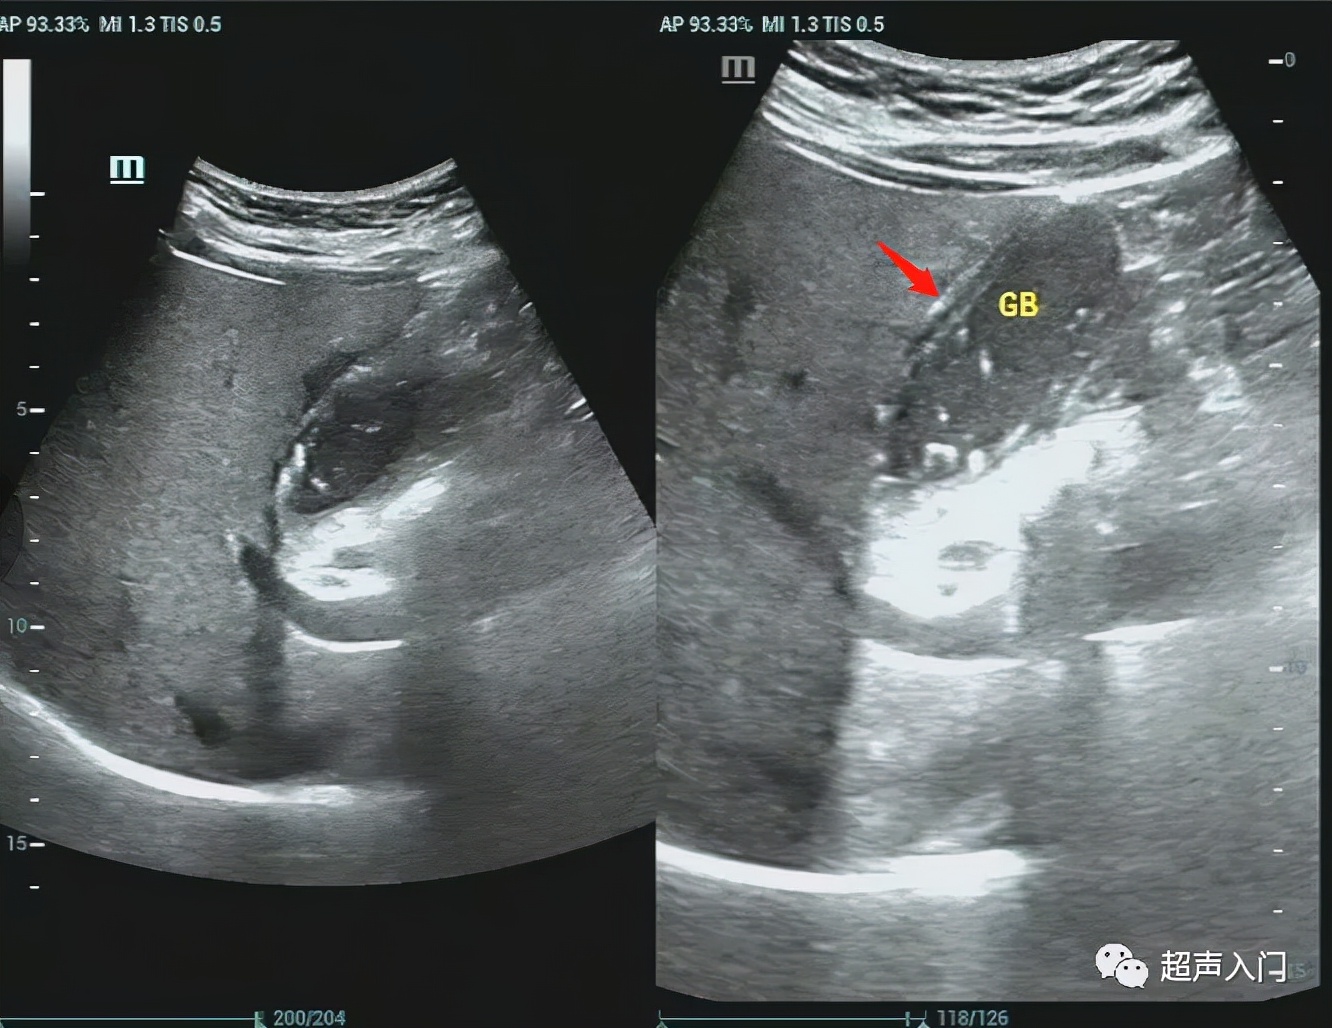

2、胆囊壁弥漫增厚,呈高回声,其间出现间断或连续的弱回声带,形成胆囊壁的“双边影”(double- laverecho)。

此征系浆膜下水肿、出血和炎性细胞浸润等改变所致。

5、多伴有胆囊结石,往往嵌顿于胆囊颈管部。

6、急性胆囊炎穿孔时,可显示胆囊壁的局部膨出或缺损,以及胆囊周围的限局性积液。